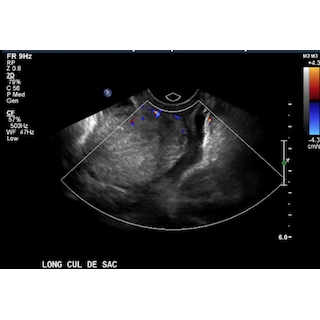

Treatment with intravenous fluids, analgesics, anti-emetics, cefazolin, and a nasogastric tube were initiated as management of acute small bowel obstruction in a stable patient. The patient was kept on dietary restrictions of nothing per mouth and vital signs were closely monitored. Further laboratory tests were conducted which revealed C-reactive protein and erythrocyte sedimentation rate within normal limits. Ten hours after admission, an upper gastrointestinal series with small bowel follow through was performed which revealed resolution of the small bowel obstruction. Case Photo #2 Transabdominal ultrasound was performed and showed trace free fluid with no ovarian, tubal, or uterine abnormalities. Case Photo #3 Case Photo #4 Case Photo #5 Case Photo #6 After these imaging tests were performed in conjunction with gradual reduction of pain, her diet progressed gradually until she was tolerating regular diet and stooling upon discharge.